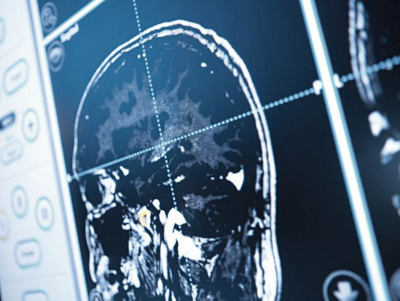

En septembre 2017, l'examen a révélé un méningiome de la taille d'un œuf au niveau du lobe frontal. La plupart du temps, les méningiomes sont des tumeurs bénignes à l'évolution lente, qui se développent à partir des enveloppes du cerveau. Ils peuvent provoquer différents symptômes en fonction de leur localisation. Le lobe frontal contrôle la force motrice, l'attention, la production d'idées et le raisonnement spatial. Il constitue aussi le siège de la personnalité individuelle. C'est la raison pour laquelle E. M. souffrait d'un grand manque d'énergie et n'était plus elle-même.